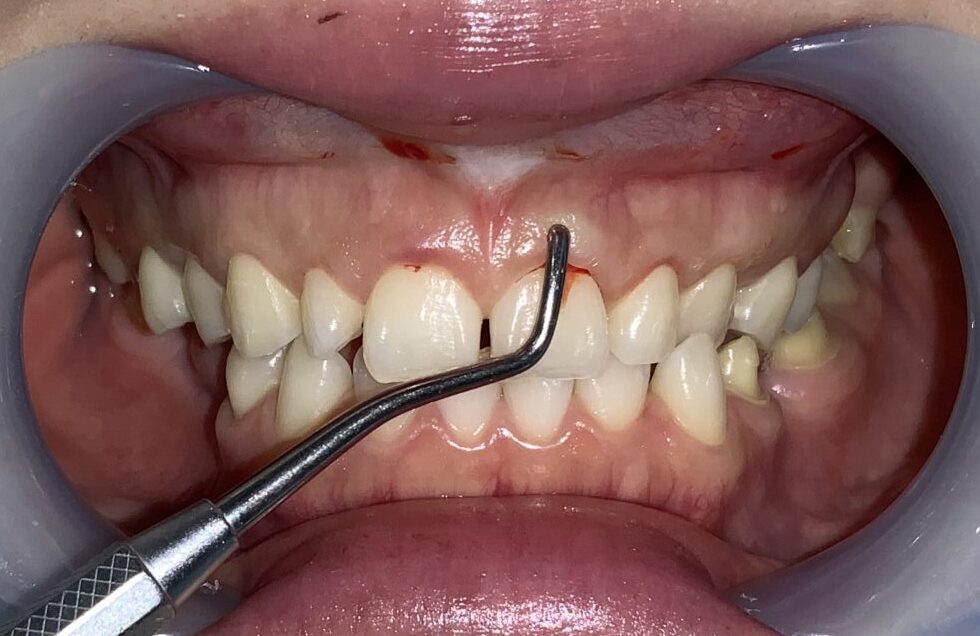

治療前の状態です。

歯の上にたくさんの歯ぐきが被っています。

前歯の歯ぐきの被り具合の検査をしています。

こちらの歯は歯ぐきの下の「歯槽骨」に尖っている部分がありそうです。

そして、歯ぐきは厚くて、歯ぐきの中に歯が埋まり込んでいる状態です。